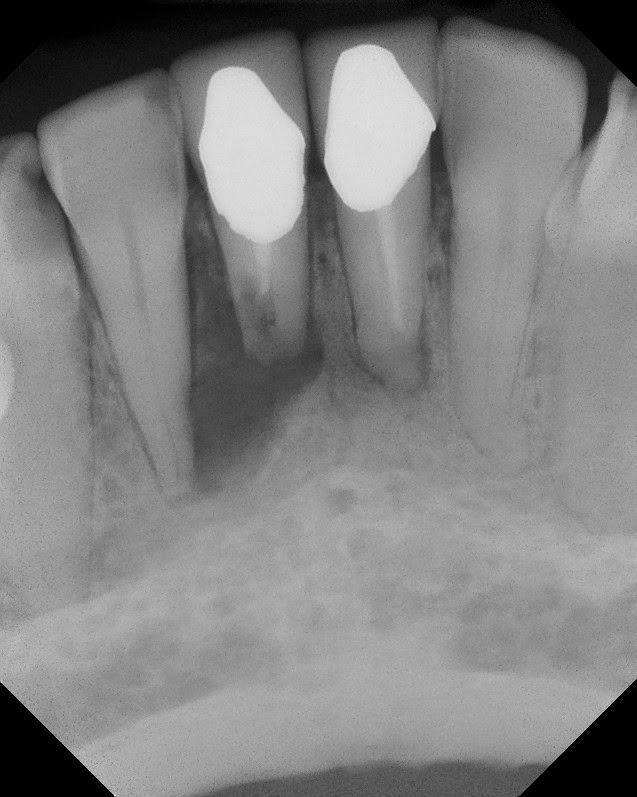

PreOp #24 and #25 - RCT done about 40 years earlier.

This patient came to Superstition Springs Endodontics in 2012. She reported trauma in the early 1970's - when one of her kids accidentally head butted those teeth. They became infected and a RCT was done in the early 70's. Original crowns still in place. Her dentists ever since have pointed out the radiolucency, but for the most part is has been mostly asymptomatic. Our exam finds #24 and #25 with mild percussion sensitivity, normal probings and class II+ mobility. We discussed the resorption that appears to have affected the apex of #25. We discussed options and she wanted to try to retain the tooth, so we decided to attempt an apicoectomy with guarded prognosis.